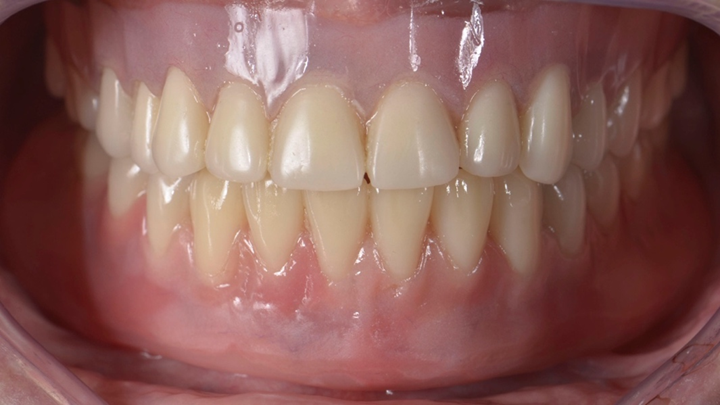

Comece o planejamento da overdenture avaliando as próteses totais do paciente (Figura 1). Se estiverem boas tanto na estética como na função, podem ser utilizadas como referência para o planejamento. Se o paciente não tem próteses totais, faça as próteses totais provisórias com a estética e função adequadas, e com a dimensão vertical de oclusão correta. Então realize tomografia computadorizada de feixe cônico pela técnica do duplo escaneamento tomográfico.